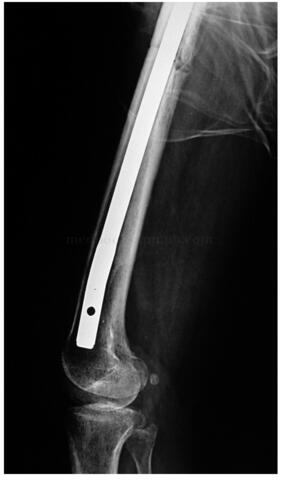

完善术前检查后行右大腿前侧间室肿瘤切除,股骨髓内针固定术。联合麻醉满意后,平卧位。采用大腿前侧梭形切口,自右髂前上棘至右髌骨下方,切除原4条手术瘢痕,自深筋膜浅层向两侧分离,分离至内外侧肌间隔。内侧分离保护股动静脉,分离结扎股神经。自内外侧肌间隔下方向股骨方向分离,至股骨表面。远端在髌骨下方切断髌腱,近端切断股四头肌的起点,其深方在股骨上的止点连同骨膜一同切除(图49‐5)。为防止因大范围切除骨膜造成股骨干病理性骨折,于股骨髁逆行置入带锁髓内针,并锁定远端锁钉(图49‐6)。充分止血,置入伤口负压引流管3 根。分层缝合伤口,术毕。

图49‐6 为预防骨折,带锁髓内针固定后

图49‐8 术后半年轻微外伤后出现右股骨干中段横断骨折,因有 预防性内固定存在,骨折无移位

:患者术后3周开始扶双拐下地运动,并进行大腿局部放疗1月。术后半年,患者轻微外伤后出现右股骨干中段横断骨折,因有预防性内固定存在,骨折无移位(图49‐8),术后1年骨折愈合(图49‐9)。目前患者术后5年,肿瘤无局部复发,无淋巴结转移,无远隔转移(图49‐10)。患者平卧位主动屈髋、屈膝无力,被动屈膝45°,屈髋45°,日常不佩戴支具扶单拐行走,也可以不扶拐行走,轻度跛行。患者自觉功能满意。